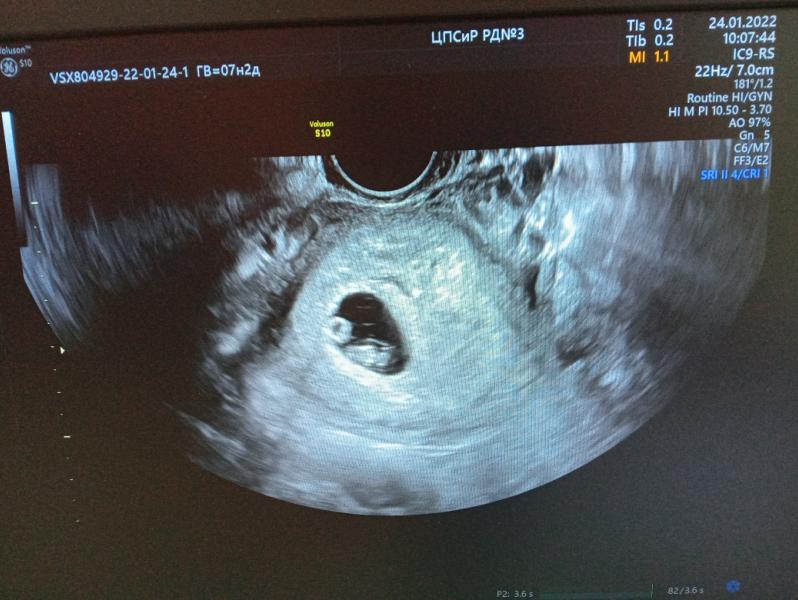

❤️ 8 недель ❤️

Меня наконец-то выписали, по УЗИ сказали, что всё стало лучше. Гипертонус ушёл, шейка матки стала длиннее. Ретрохориальная гематома как была, так и осталась.